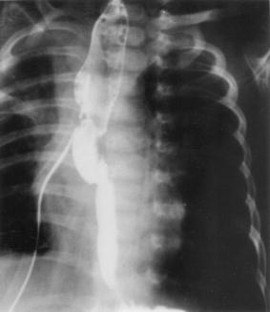

Fig. 4